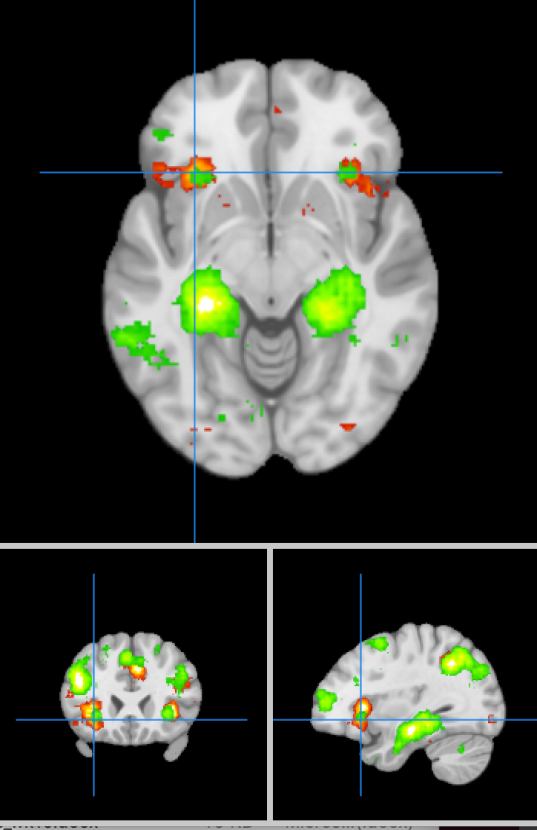

Neurosynth terms: executive function and memory.

Neurosynth map for the terms